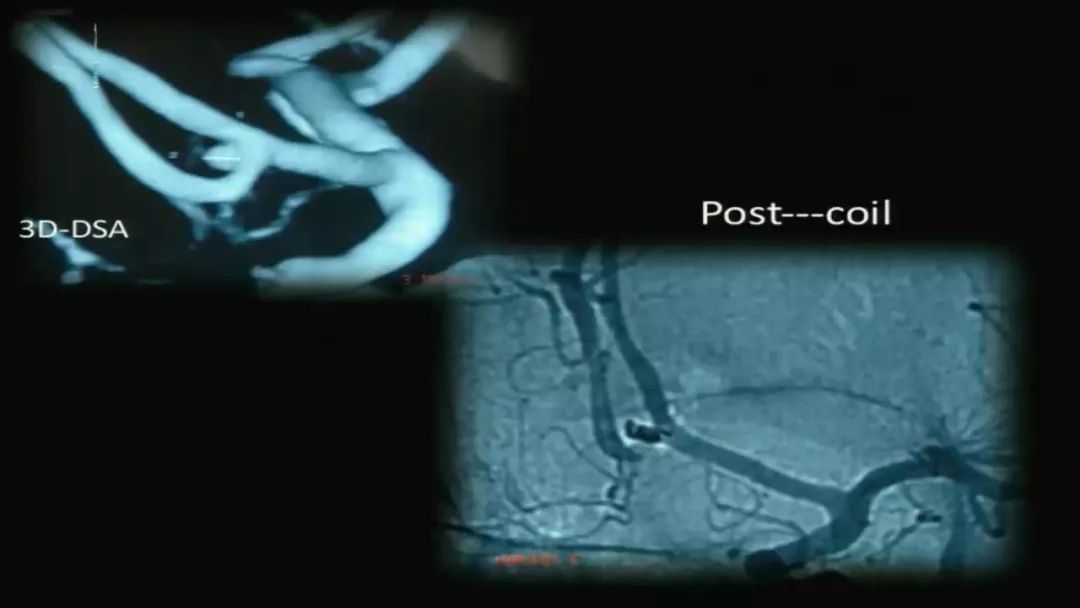

王智教授:从复合型医生的角度看待脑动脉瘤治疗的选择